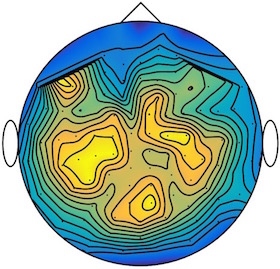

This results in two classes of recordings, one for each pressed button. We aim at computing a representative activity map for each class using Wasserstein barycenters. For each class we have recordings each having samples located on the vertices of an hexahedral mesh of a hemisphere (corresponding to a MEG recording helmet). These recorded values are positive by construction, and we rescale them linearly to impose . Figure 6, top row, shows some samples from this dataset, displayed using interpolated colors as well as iso-level curves. The black dots represent the position of the electrodes on the half-sphere of the helmet, flattened on a 2-D disk.

We computed TV-regularized barycenters independently for each class by solving (16) with the TV regularization using the projected gradient descent method (22). We used a squared Euclidean metric (24) on the flattened hemisphere. Since the data is defined on an irregular graph, instead of (23), we use a graph-based discrete gradient. We denote the graph which connects neighboring electrodes. The gradient operator on the graph is

The total variation on this graph is then obtained by using , the norm, i.e. we use in (23).

Figure 6 compares the naive barycenters (i.e. the usual mean), barycenters obtained without regularization (i.e. ) and barycenters computed with an increasing regularization strength . The input histograms being very noisy, the use of regularization is important to make the area of significant activity emerge from the noise. The use of a TV regularization helps to keep a sharp transition between active and non-active regions.